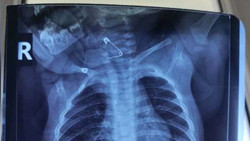

Одиннадцатимесячный младенец проглотил булавку в Оше. Фото